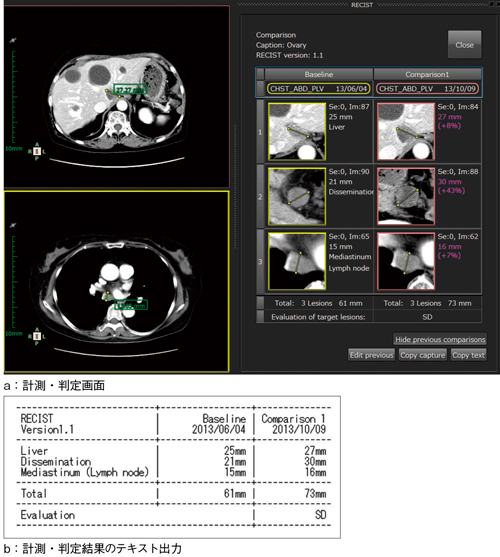

図5 RECIST計測ツール

a:標的病変(target lesion)が定義された過去検査と当時の測定状況は,すぐに呼び出せる。画面の指示に従って計測を行うことで,治療効果判定や径和計算を自動的に行う。

b:テキストで出力された結果は,レポートにそのまま貼り付けが可能。